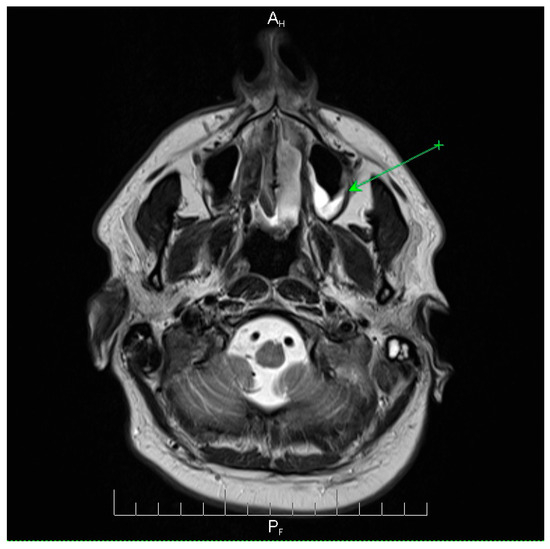

Neuroimaging—including CT and subsequent MRI—demonstrated mild sinus opacification and mastoid involvement, without evidence of parenchymal lesions or thrombosis (Table 4).

Neuroimaging revealed mild ethmoidal/sphenoidal sinus opacification and left mastoid air cell involvement without evidence of parenchymal lesions or venous sinus thrombosis (Figure 1, Figure 2 and Figure 3). Coronal and axial T2-weighted MRI sequences revealed para-fluid collections within the left mastoid air cells extending toward Citelli’s angle (Figure 1, Figure 2 and Figure 3), consistent with an otogenic focus and a possible contiguous route for intracranial spread.

Figure 2.

Axial T2-weighted MRI scan demonstrating opacification of the left mastoid air cells with a hyperintense signal (green arrow), indicative of mastoid involvement. This finding suggests a potential contiguous source of intracranial infection in this patient. No acute lesions, hemorrhage, or signal abnormalities were observed in the cerebellum or brainstem, and the surrounding brain parenchyma appeared normal. These imaging features support localized mastoid pathology without evidence of intracranial extension, providing important radiological context for the patient’s clinical presentation and aiding in the assessment of the infection risk. AH = anterior-head. PF = posterior- foot.